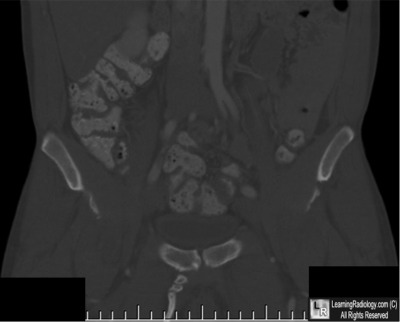

Additional Images - Coronal Reformatted CT of Pelvis

Coronal Reformatted CT of Pelvis

3. Pelvic Digit

Pelvic Digit

• Rare congenital anomaly

• Bone develops in soft tissue

• Can arise from any of the pelvic bones; also anterior abdominal wall

• Most commonly arises from ilium

• Unilateral

• Believed to arise in mesenchymal stage of bone growth within first 6 weeks of embryogenesis